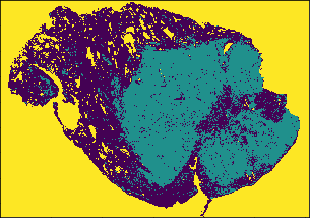

Lung cancer is one of the most deadly cancers (Siegel, Miller and Jemal, 2020). One of the most common types of lung cancer is adenocarcinoma which accounts for about 40% of all lung cancers (Zappa and Mousa, 2016) and has various morphological features (Matsuda and Machii, 2015). We use 230 pathology images of 133 lung adenocarcinoma patients in the National Lung Screening Trial (NLST) data. All images are obtained under 40X magnification, and the median size of images is 24,24419,261 pixels. The image patches of size 300300 pixels (7575 microns) are segmented into three classes of the tumor, normal, and empty regions using a deep convolutional neural network (CNN) (Wang et al., 2018). For example, for a given NLST pathology image of size 30,00030,000, the CNN model generates the segmented image of size 100100. We implement an additional pre-processing step to remove noise: a single pixel is considered to be noise when its class is different from the surrounding eight singular-class pixels, and the noise pixels are reclassified to the class of the surrounding pixels. The denoised three-class images are transformed using the SEDT-3. Figure 5 presents the pathology image, the segmented three-class image of Wang et al. (2018), and the SEDT-3 image.

A sequence of cubical complices is constructed using the SEDT-3 values as filtration, and persistent homology is computed using GUDHI (Dlotko, 2015). We replace the dimension-zero result with infinite death value with and exclude the dimension-one result with infinite death value to remove features related to empty regions. The median number of the computed features per image slice is 694 for dimension-zero and 1,768 for dimension-one. The ranges of persistence diagrams are for dimension-zero and for dimension-one. The smoothing parameters and are used for the persistence surface functions.